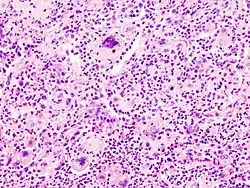

Ausgeprägte Amyloidablagerungen (homogen rosa) in einem Lymphknoten, H&E.

Amyloidablagerungen in den Gefäßwänden, H&E.